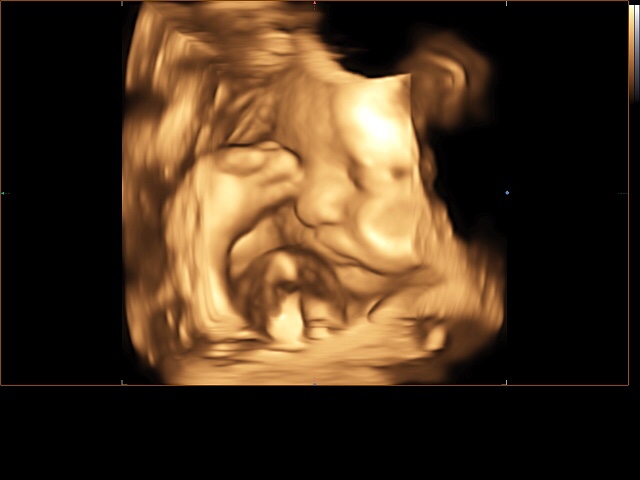

А вот и наш третий скрининг)))) все в норме! По весу 1800. Врач сказала хороший щекастый мальчик с большой морковкой 😂😂😂😂

Делали 4д с записью на диск видио и фото